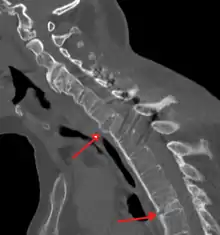

CT scan showing bamboo spine in ankylosing spondylitis

X-rays

The earliest changes demonstrable by plain X-ray shows erosions and sclerosis in sacroiliac joints. Progression of the erosions leads to widening of the joint space and bony sclerosis. X-ray spine can reveal squaring of vertebrae with bony spur formation called syndesmophyte. This causes the bamboo spine appearance. A drawback of X-ray diagnosis is the signs and symptoms of AS have usually been established as long as 7–10 years prior to X-ray-evident changes occurring on a plain film X-ray, which means a delay of as long as 10 years before adequate therapies can be introduced.[24]